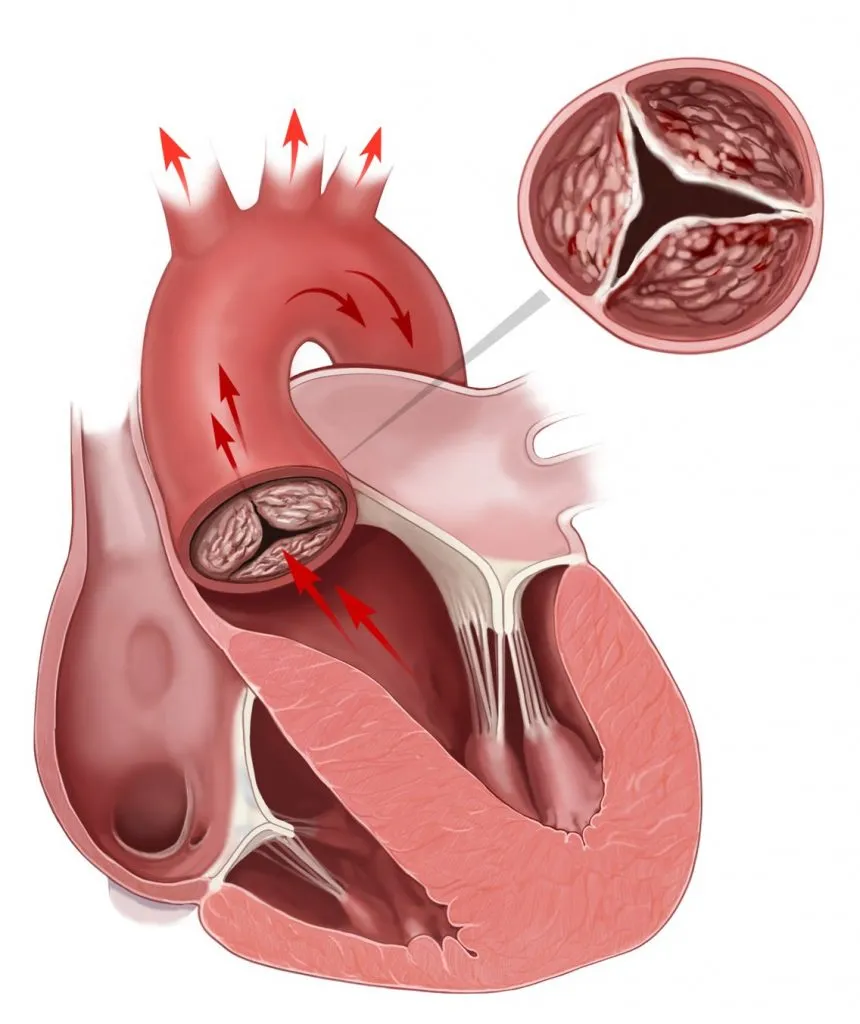

Изображения, связанные с атеросклерозом нижних конечностей и его лечением